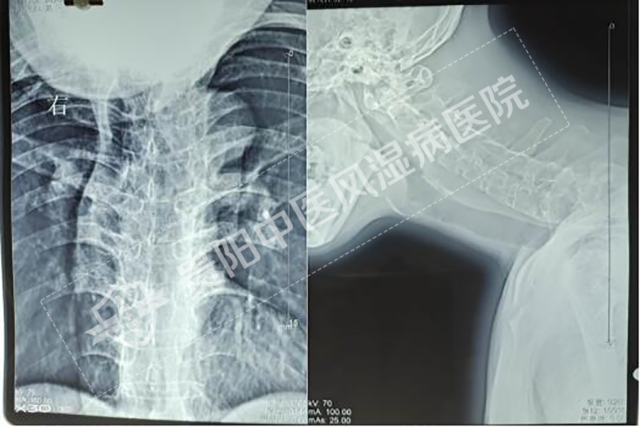

一大早,義診現(xiàn)場(chǎng)人頭攢動(dòng)、絡(luò)繹不絕,很多患者拿著X光片、CT片、核磁共振片前來(lái)問(wèn)診咨詢,貴陽(yáng)強(qiáng)直醫(yī)院風(fēng)濕免疫科主任張振華、B超影像科主任石春燕以�?茖I(yè)的角度,對(duì)前來(lái)義診的群眾提供疾病咨詢及指導(dǎo),對(duì)骨關(guān)節(jié)炎、關(guān)節(jié)置換術(shù)后等相關(guān)知識(shí)進(jìn)行了科普宣傳,義診現(xiàn)場(chǎng)還安排了免費(fèi)測(cè)血壓、血糖,免費(fèi)測(cè)骨密度檢查等內(nèi)容�,F(xiàn)場(chǎng)氣氛熱烈,受到廣大群眾的一致好評(píng)。